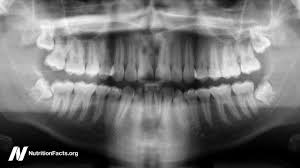

Panoramic Taken On Our Office On A 10 Year Old Child Showing Permanents As Well As Primary Teeth Unerupted Dental Treatment Dental Clinic Dental